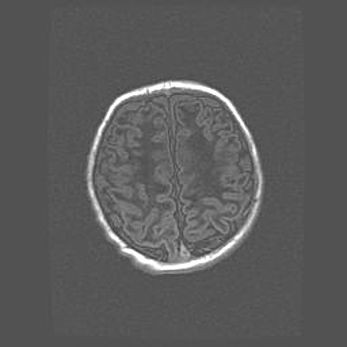

Церебральная ишемия II.

Возраст: 7 дней

Вес: 3350 г

Пол: женский

Окружность головы: 35 см

Срок гестации: 39 недель

Ишемия головного мозга – это состояние, которое развивается в ответ на кислородное голодание вследствие недостаточного мозгового кровообращения. У новорожденных она является следствием дефицита кислорода, что ведет к метаболическим расстройствам различной степени тяжести в тканях головного мозга, в том числе к развитию коагуляционных некрозов и гибели нейронов.